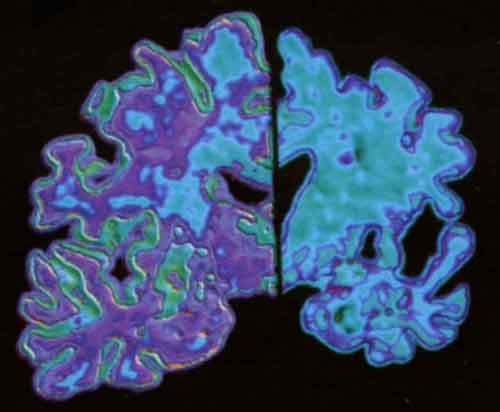

Alzheimer: attenzione ai vuoti di memoria in soggetti anziani

Ad esempio, la difficolta’ a ricordare la strada di casa in un ambiente di strade familiari era una delle situazioni maggiormente associate a danni cognitivi, mentre la difficolta’ a ricordare le cose che si erano appena viste era piu’ che altro legata al normale invecchiamento. “Queste scoperte suggeriscono che i medici di base dovrebbero prestare grande attenzione alla denuncia, da parte degli anziani, di episodi di questo genere, perche’ spesso possono tradire la necessita’ di compiere ulteriori valutazioni cliniche che possono essere cruciali nella lotta contro l’Alzheimer”, ha spiegato Rebecca Amariglio, fra gli autori dello studio.